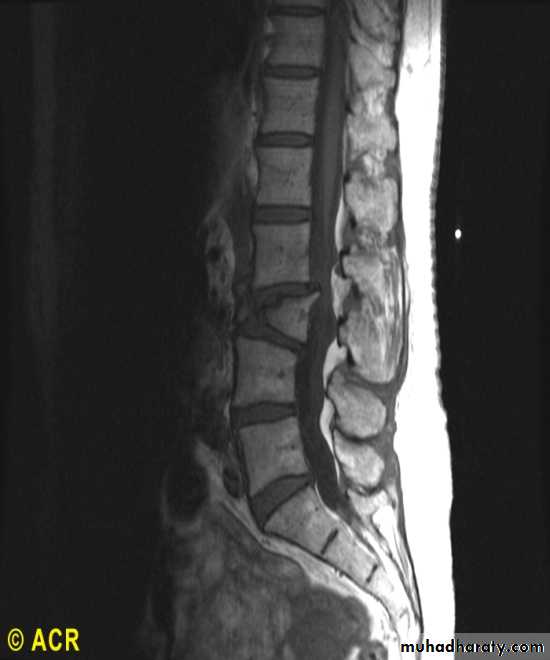

Compression fracture: lumbar spine (MRI)